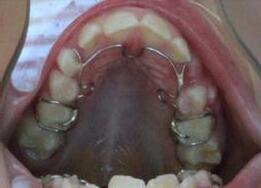

Maxillary and mandibular impressions were taken in irreversible hydrocolloid impression material. Both TMJ discs were recaptured in the Phonetic bite,6 which was recorded with the PVS bite recording material (Blue Bite). The therapeutic splint was fabricated, tried, inserted, and verified that the displaced discs were recaptured. This splint must be worn 24/7, except brushing the teeth, eating and sports (6-A, B, C, D, E).

FIG. 6A: Phonetic bite

FIG. 6B: Therapeutic splint

FIG. 6C: Splint in situ, frontal view

FIG. 6D: Splint in situ, right lateral view

FIG. 6E: Splint in situ, left lateral view